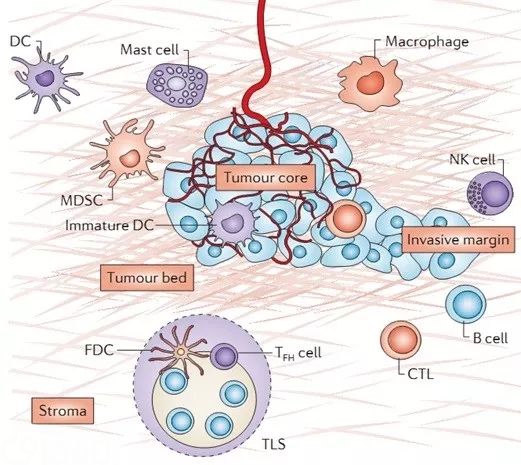

肿瘤浸润淋巴细胞和免疫评分-肿瘤预后判断系统的完美补充 – 91360智慧病理网